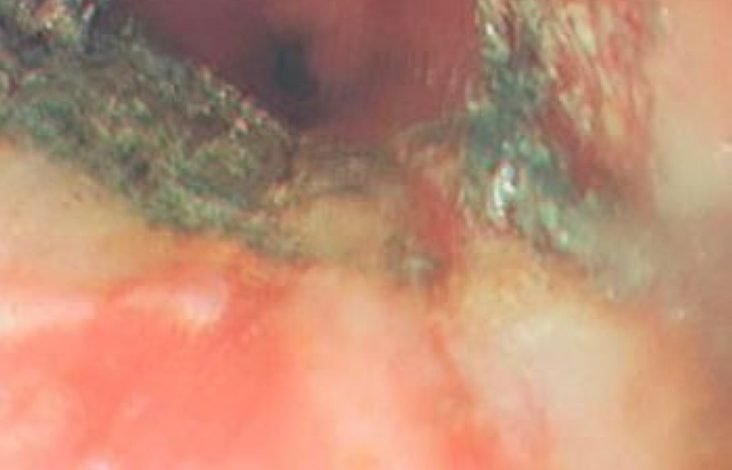

تمكن فريق طبي بمستشفى الولادة والأطفال بمكة المكرمة بقيادة استشاري الجهاز الهضمي الدكتور علي الشمراني من إنقاذ حياة طفلة غير سعودية تبلغ من العمر 4 سنوات ابتلعت بطارية حارقة. وتم نقل الطفلة إلى طوارئ المستشفى بعد مرور ١٢ ساعة على ابتلاعها للبطارية، حيث ذابت المادة الكيميائية حول البطارية ما أدى إلى حروق في منطقة المريء الوسطى في طبقتين على الأقل أحدثت نزفاً دموياً تمت السيطرة عليه، حيث تم التعامل مع النزف ونزع البطارية واستخراجها، وهي تخضع للعلاج الطبي بالمستشفى للاطمئنان على صحتها.